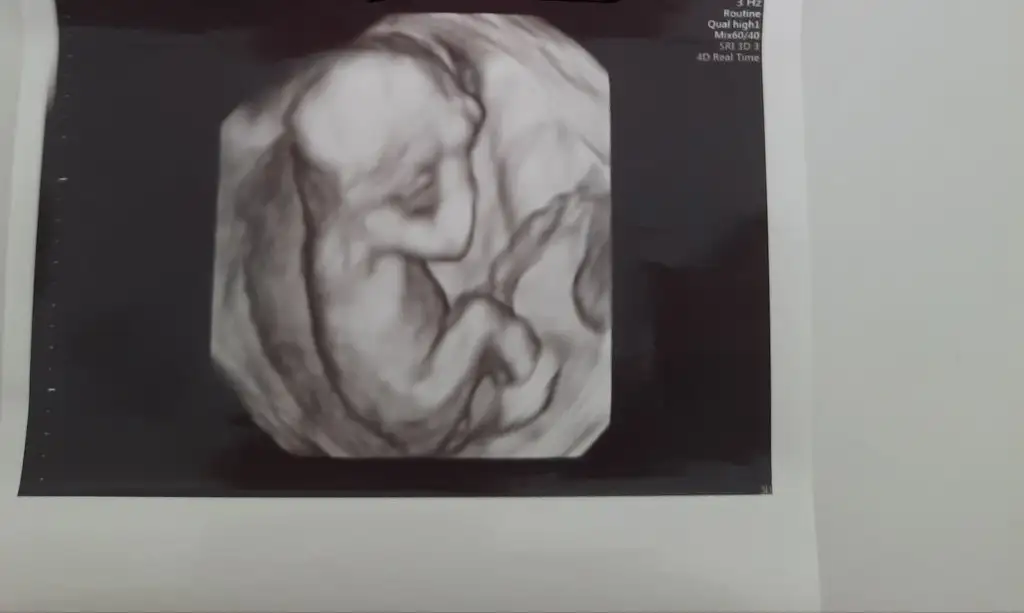

Merhaba cinsiyet tahmininde bulunabilirmisiniz acaba doktorum önce kız sonra erkek dediNub gözükmüyor canım

Hanımlar tecrübeli anneler cinsiyet tahmini yapabilir mi acaba

Merhaba cinsiyet tahmininde bulunabilirmisiniz acaba doktorum önce kız sonra erkek dediEki Görüntüle 2839553

Canım çok anlamıyorum ben ama bacak arasında bişey yok gibi :)Hanımlar tecrübeli anneler cinsiyet tahmini yapabilir mi acaba

Canım çok anlamıyorum ben ama bacak arasında bişey yok gibi :)

Ey yarabbi bide arkasını dönmüşHanımlar tecrübeli anneler cinsiyet tahmini yapabilir mi acaba

Maşallah şu bacak arasında sanki bişey saklıHanımlar tecrübeli anneler cinsiyet tahmini yapabilir mi acaba